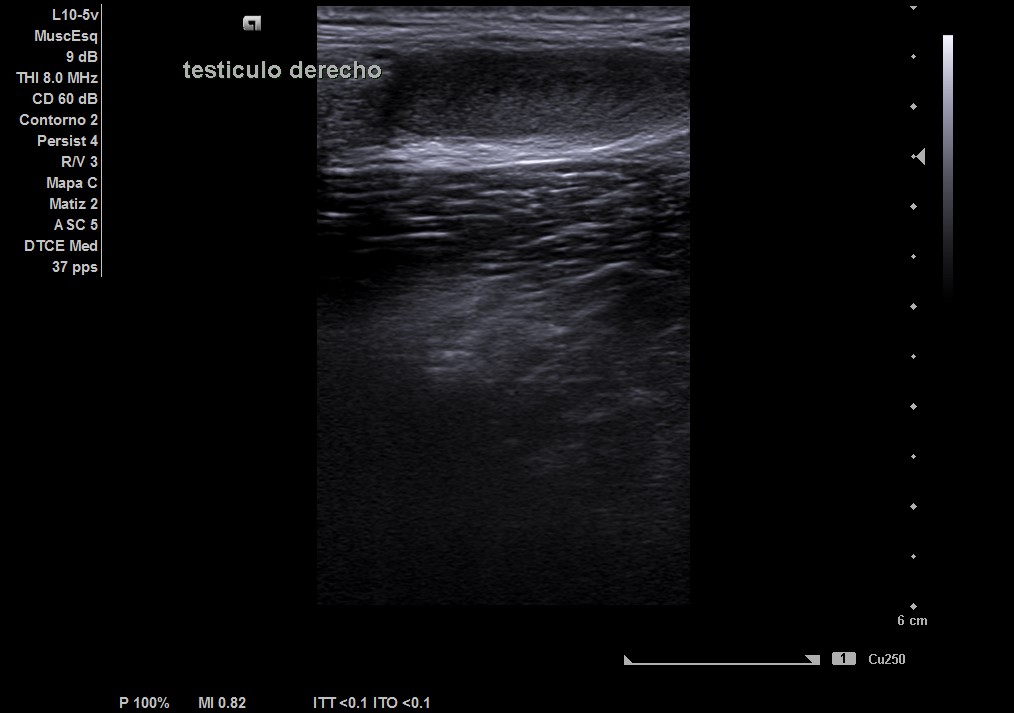

Durante la realización de la prueba, el paciente comenta que en ocasiones no encuentra el testículo derecho. Por lo que decidimos cambiar a la sonda lineal y explorar planos más superficiales donde observamos el testículo derecho, por encima del ligamento inguinal, en fosa ilíaca derecha con ecoestructura normal, homogénea y vascularización normal.